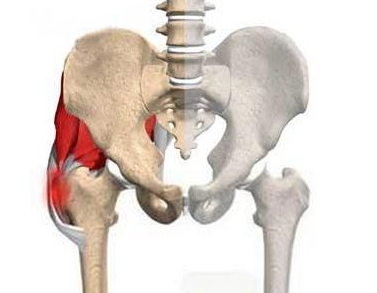

郑州治疗骨科医院讲解股骨头坏死髓腔减压术是什么?

郑州治疗骨科医院介绍到股骨头坏死常常是由于不良的生活习惯引起的,比如过度的饮酒,长期…[详情]